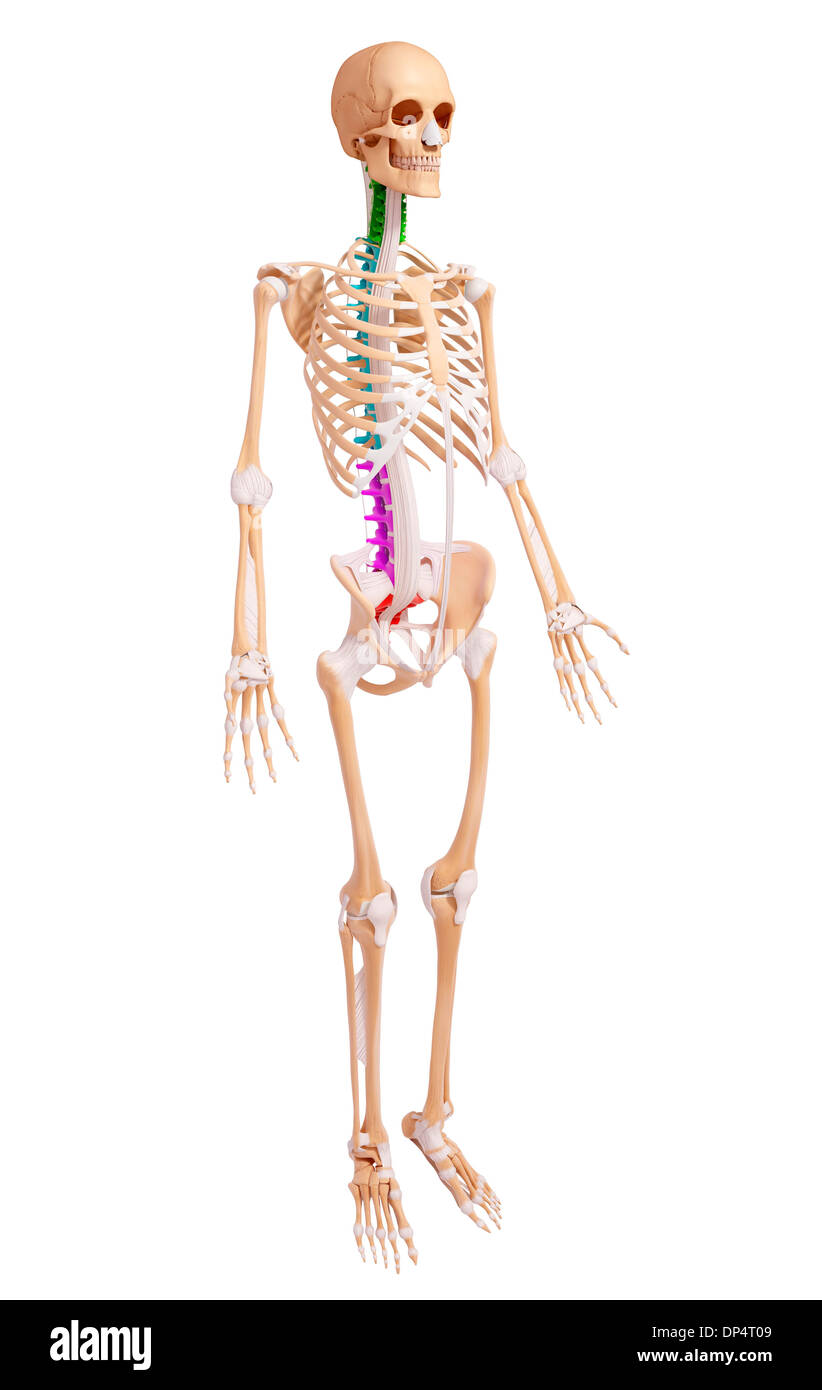

Human Skeleton, artwork Banque D'Imageshttps://www.alamyimages.fr/image-license-details/?v=1https://www.alamyimages.fr/human-skeleton-artwork-image65260169.html

Human Skeleton, artwork Banque D'Imageshttps://www.alamyimages.fr/image-license-details/?v=1https://www.alamyimages.fr/human-skeleton-artwork-image65260169.htmlRFDP4T09–Human Skeleton, artwork